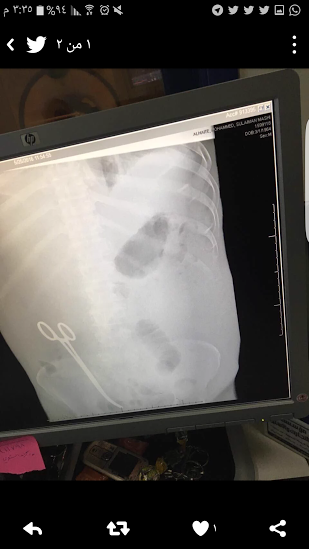

أصدرت المديرية العامة للشئون الصحية بمنطقة حائل، بالمملكة العربية السعودية، اليوم الجمعة، بيانًا اعتذرت فيه عن واقعة نسيان "مقص" داخل بطن مريض أثناء عملية جراحية له.

وقالت صحة حائل في البيان إنها تأسف، وتقدم اعتذارها لما حدث للمريض، وتود أن توضح أنه فور العلم بذلك تم الإبلاغ عن هذا الحدث الجسيم فور وقوعه وتسجيله عبر برنامج الأحداث الطبية الجسيمة في وزارة الصحة، وكذلك تم توجيه مدير عام الشئون الصحية بالمنطقة بالتحقيق في أسباب حدوث ذلك وملابساته ومحاسبة المتسبب فيه.

وأضافت أنه تم منع جميع من شارك بهذا الخطأ من الممارسين الصحيين المتعاقدين من السفر حتى انتهاء التحقيق، وذلك لتؤكد للجميع حرصها التام على صحة وسلامة المرضى.

وأكدت صحيفة "عاجل" السعودية، أن الطبيب الوافد صاحب الواقعة، هو مصري الجنسية، وجدير بالذكر، أن إدارة مستشفى الملك خالد بحائل، حققت مع الطبيب المصري، إثر اتهام مريض له بنسيان مقص طبي في بطنه، بعد عملية أجراها له حيث أحس المريض بألم شديد في بطنه بعد العملية، وقام بعمل أشعة وتبين وجود المقص؛ إثر العملية السابقة.